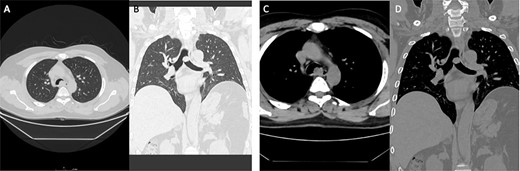

A 34-year-old female, who is a known case of ulcerative colitis, has been followed by a pulmonologist due to a chronic cough, that was first treated as asthma; but did not resolve with the management plan set by the pulmonology service. A CT scan (Fig. 1) was then conducted on this patient that showed right endobronchial lesion. Afterwards, this patient underwent bronchoscopy and a biopsy was taken from the cherry-like lesion mentioned. Pathology confirmed the diagnosis to be a typical carcinoid tumor (Fig. 1; case 1). The decision was made by the treating team to take the patient for tissue-sparing endobronchial resection. During the operation, the lesion was identified in the right intermedius bronchus, and by the use of a bronchoscopic snare and electrocautery, it was separated and removed en bloc.

Case 1: (A and B) Lung window showing endo-bronchial lesion at the right bronchus intermedius with air trapping middle and lower lobes. (C and D) Same lesion evident on mediastinal window on both axial and coronal cuts.